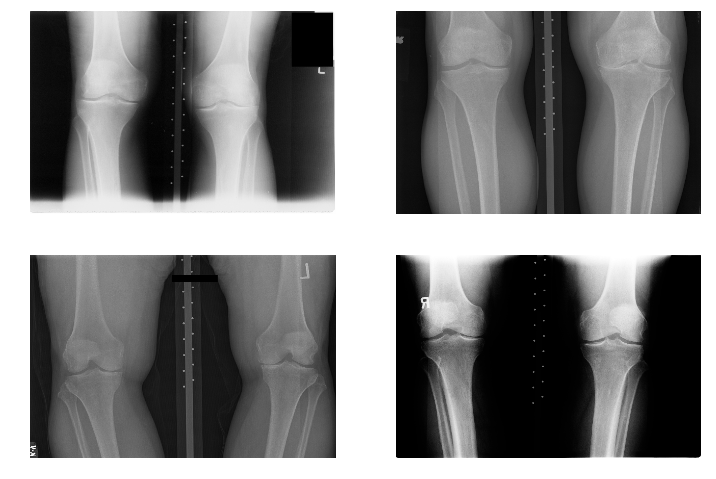

The data used for the experiments and analysis in this study are bilateral PA fixed flexion knee X-ray images. Figure 3 shows some samples of knee X-ray images from the dataset. Due to variations in X-ray imaging protocols, there are some visible artefacts in the X-ray images (Figure 3).

Refer to caption

Figure 3: Samples of bilateral PA fixed flexion knee OA radiographs.

The datasets are from the Osteoarthritis Initiative (OAI) and Multicenter Osteoarthritis Study (MOST) in the University of California, San Francisco. These are standard public datasets used in knee osteoarthritis studies.